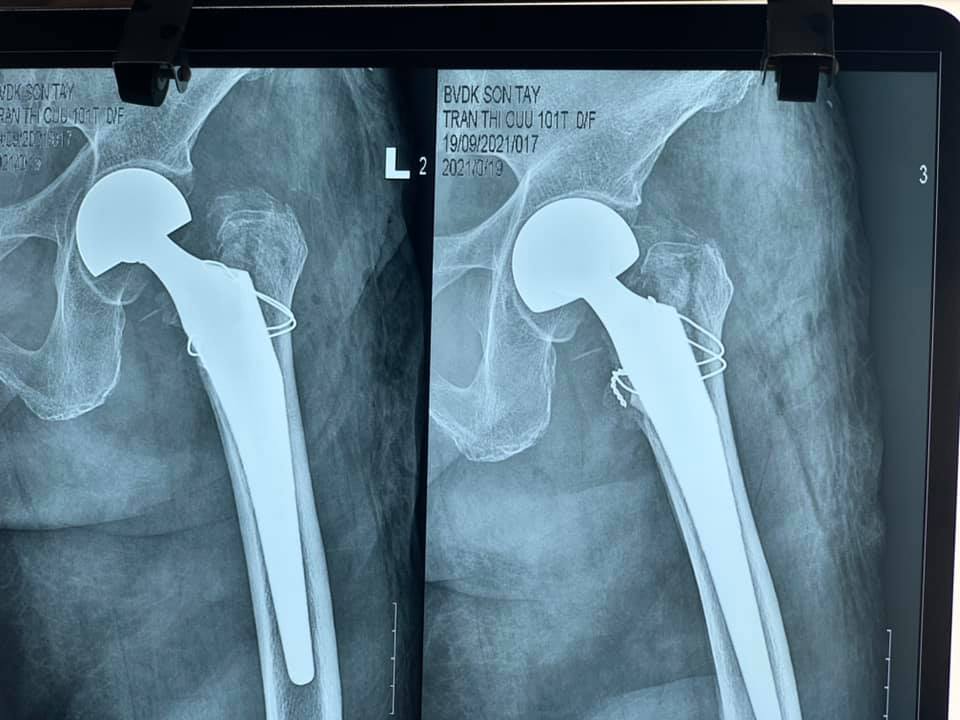

Gần đây nhất là trường hợp cụ bà Trần Thị C, 101 tuổi, ở Đông Quang – Ba Vì – Hà Nội bị gãy kín Liên mấu chuyển xương đùi trái do ngã ngày thứ nhất, bệnh nhân có bệnh lý tim mạch, tăng huyết áp, thiếu máu, suy kiệt.

Tiến hành làm các xét nghiệm, siêu âm, chụp X- quang, các bác sĩ nhận định đây là một trường hợp cần được phẫu thuật sớm, có thể cho bệnh nhân sớm ngồi dậy, tập luyện để tránh các biến chứng. Chỉ sau 1 ngày, bệnh nhân được phẫu thuật thay khớp háng trái nhân tạo bán phần không xi măng. Vượt qua những khó khăn trước phẫu thuật do tình trạng sức khỏe chung và bệnh lý nền kết hợp của bệnh nhân, kíp phẫu thuật đã kết hợp với kíp gây mê tiến hành thành công ca phẫu thuật, giúp cho người bệnh có cơ hội sớm bước đi trở lại.